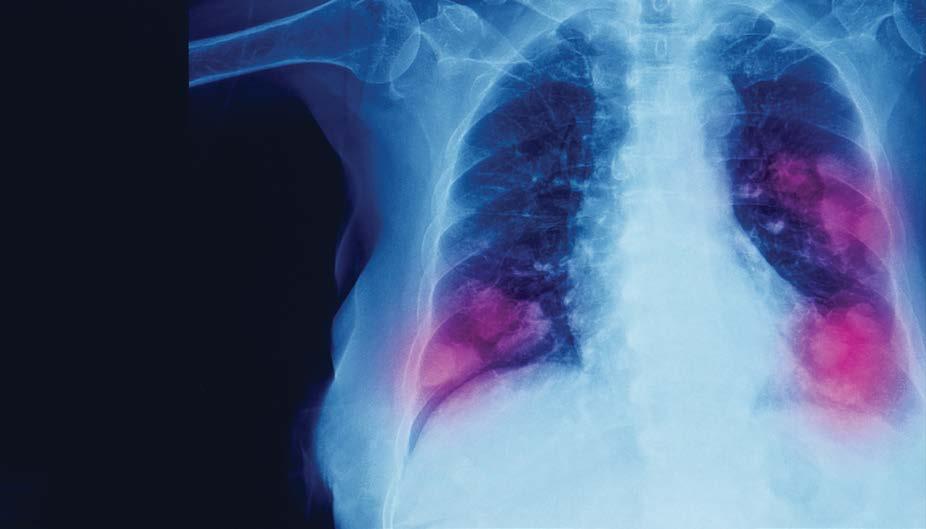

In the 27-county Rochester region from which Wilmot Cancer Institute draws patients, the lung cancer incidence rate is a startling 70 cases per 100,000 people. That’s much higher than in all of New York State, at 58 cases, and in the U.S., which is about 53 cases per 100,000 people.

Lung cancer is the second most common cancer in the U.S. and the leading cause of cancer deaths in men and women. As in the case of Maria Valeria Hernandez Quintana, 20 percent of lung cancer patients have never smoked.

Detecting lung cancer early, at stage 1, is a key to survival.

Strong Memorial Hospital and affiliates offer low-dose CT scans to screen those who qualify. The scan shows detailed images of the lungs and air tubes, and can pick up small tumors, using less radiation than conventional CT scans but with more specificity than chest x-rays.

Studies show that individuals whose cancers are detected via low-dose CTs are 20 percent less likely to die from lung cancer than those who received chest x-rays, Rivera says.